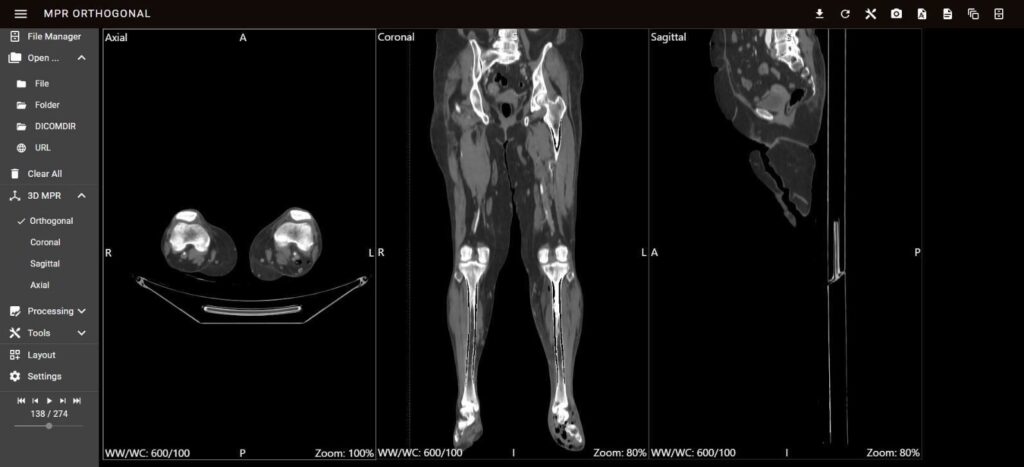

The MPV module, depicted in Figure 6, was instrumental in facilitating the detailed exploration of 2D DICOM images across multiple planes. This module’s advanced capabilities enable clinicians to obtain comprehensive views of the anatomical structures of the PAD. The implementation of a PWA provided seamless access across various devices, significantly enhancing the platform’s usability.

The MPV module is accessible via the RESTful API endpoint/api/visualization/mpv/, which allows for efficient integration and data retrieval. This API endpoint supports various functionalities, including the collection of DICOM images, metadata retrieval, and real-time updates. The interactive tools for zooming, panning, and navigating through different planes (axial, sagittal, and coronal) are seamlessly integrated through this API, enabling the precise examination of specific regions of interest. These capabilities ensure that clinicians can interact with the visualization data dynamically, facilitating real-time adjustments and increasing diagnostic accuracy. The robust architecture of the MPV module, combined with its API-driven approach, ensures that the visualization tools are both scalable and adaptable to different clinical requirements. This integration not only improves the efficiency of data handling and processing but also ensures that the visualization remains consistent and reliable across various use cases and devices. Thus, the MPV module, with its advanced interface and RESTful API support, significantly enhances the diagnostic process and treatment planning for PAD.

The module uses IndexDB for local storage, allowing the browser to store large amounts of structured data [31]. This is essential for managing the vast datasets involved in medical imaging. The data are retrieved via GET requests and processed in JSON format, ensuring compatibility and ease of manipulation. The frontend platform services interact with the visualization components to render multiplanar views of the DICOM images. Users can navigate through different planes (axial,

sagittal, and coronal) to examine specific regions of interest. This functionality is crucial for accurate diagnosis and treatment planning.

4.1.2. User Interaction and Visualization

The PWA approach enables seamless DICOM store connectivity, allowing users to search for and load specific studies for detailed analysis. Interactive viewers control support zooming, panning, and resetting, improving user engagement and interaction. The functionality of reference lines and planes is tailored to create spatial relationships within the MPR views, facilitating the alignment and comparison of DICOM images. This integration of reference lines involves constructing 3D lines and planes and coordinating transformations to convert 3D patient points to 2D pixel coordinates [32].